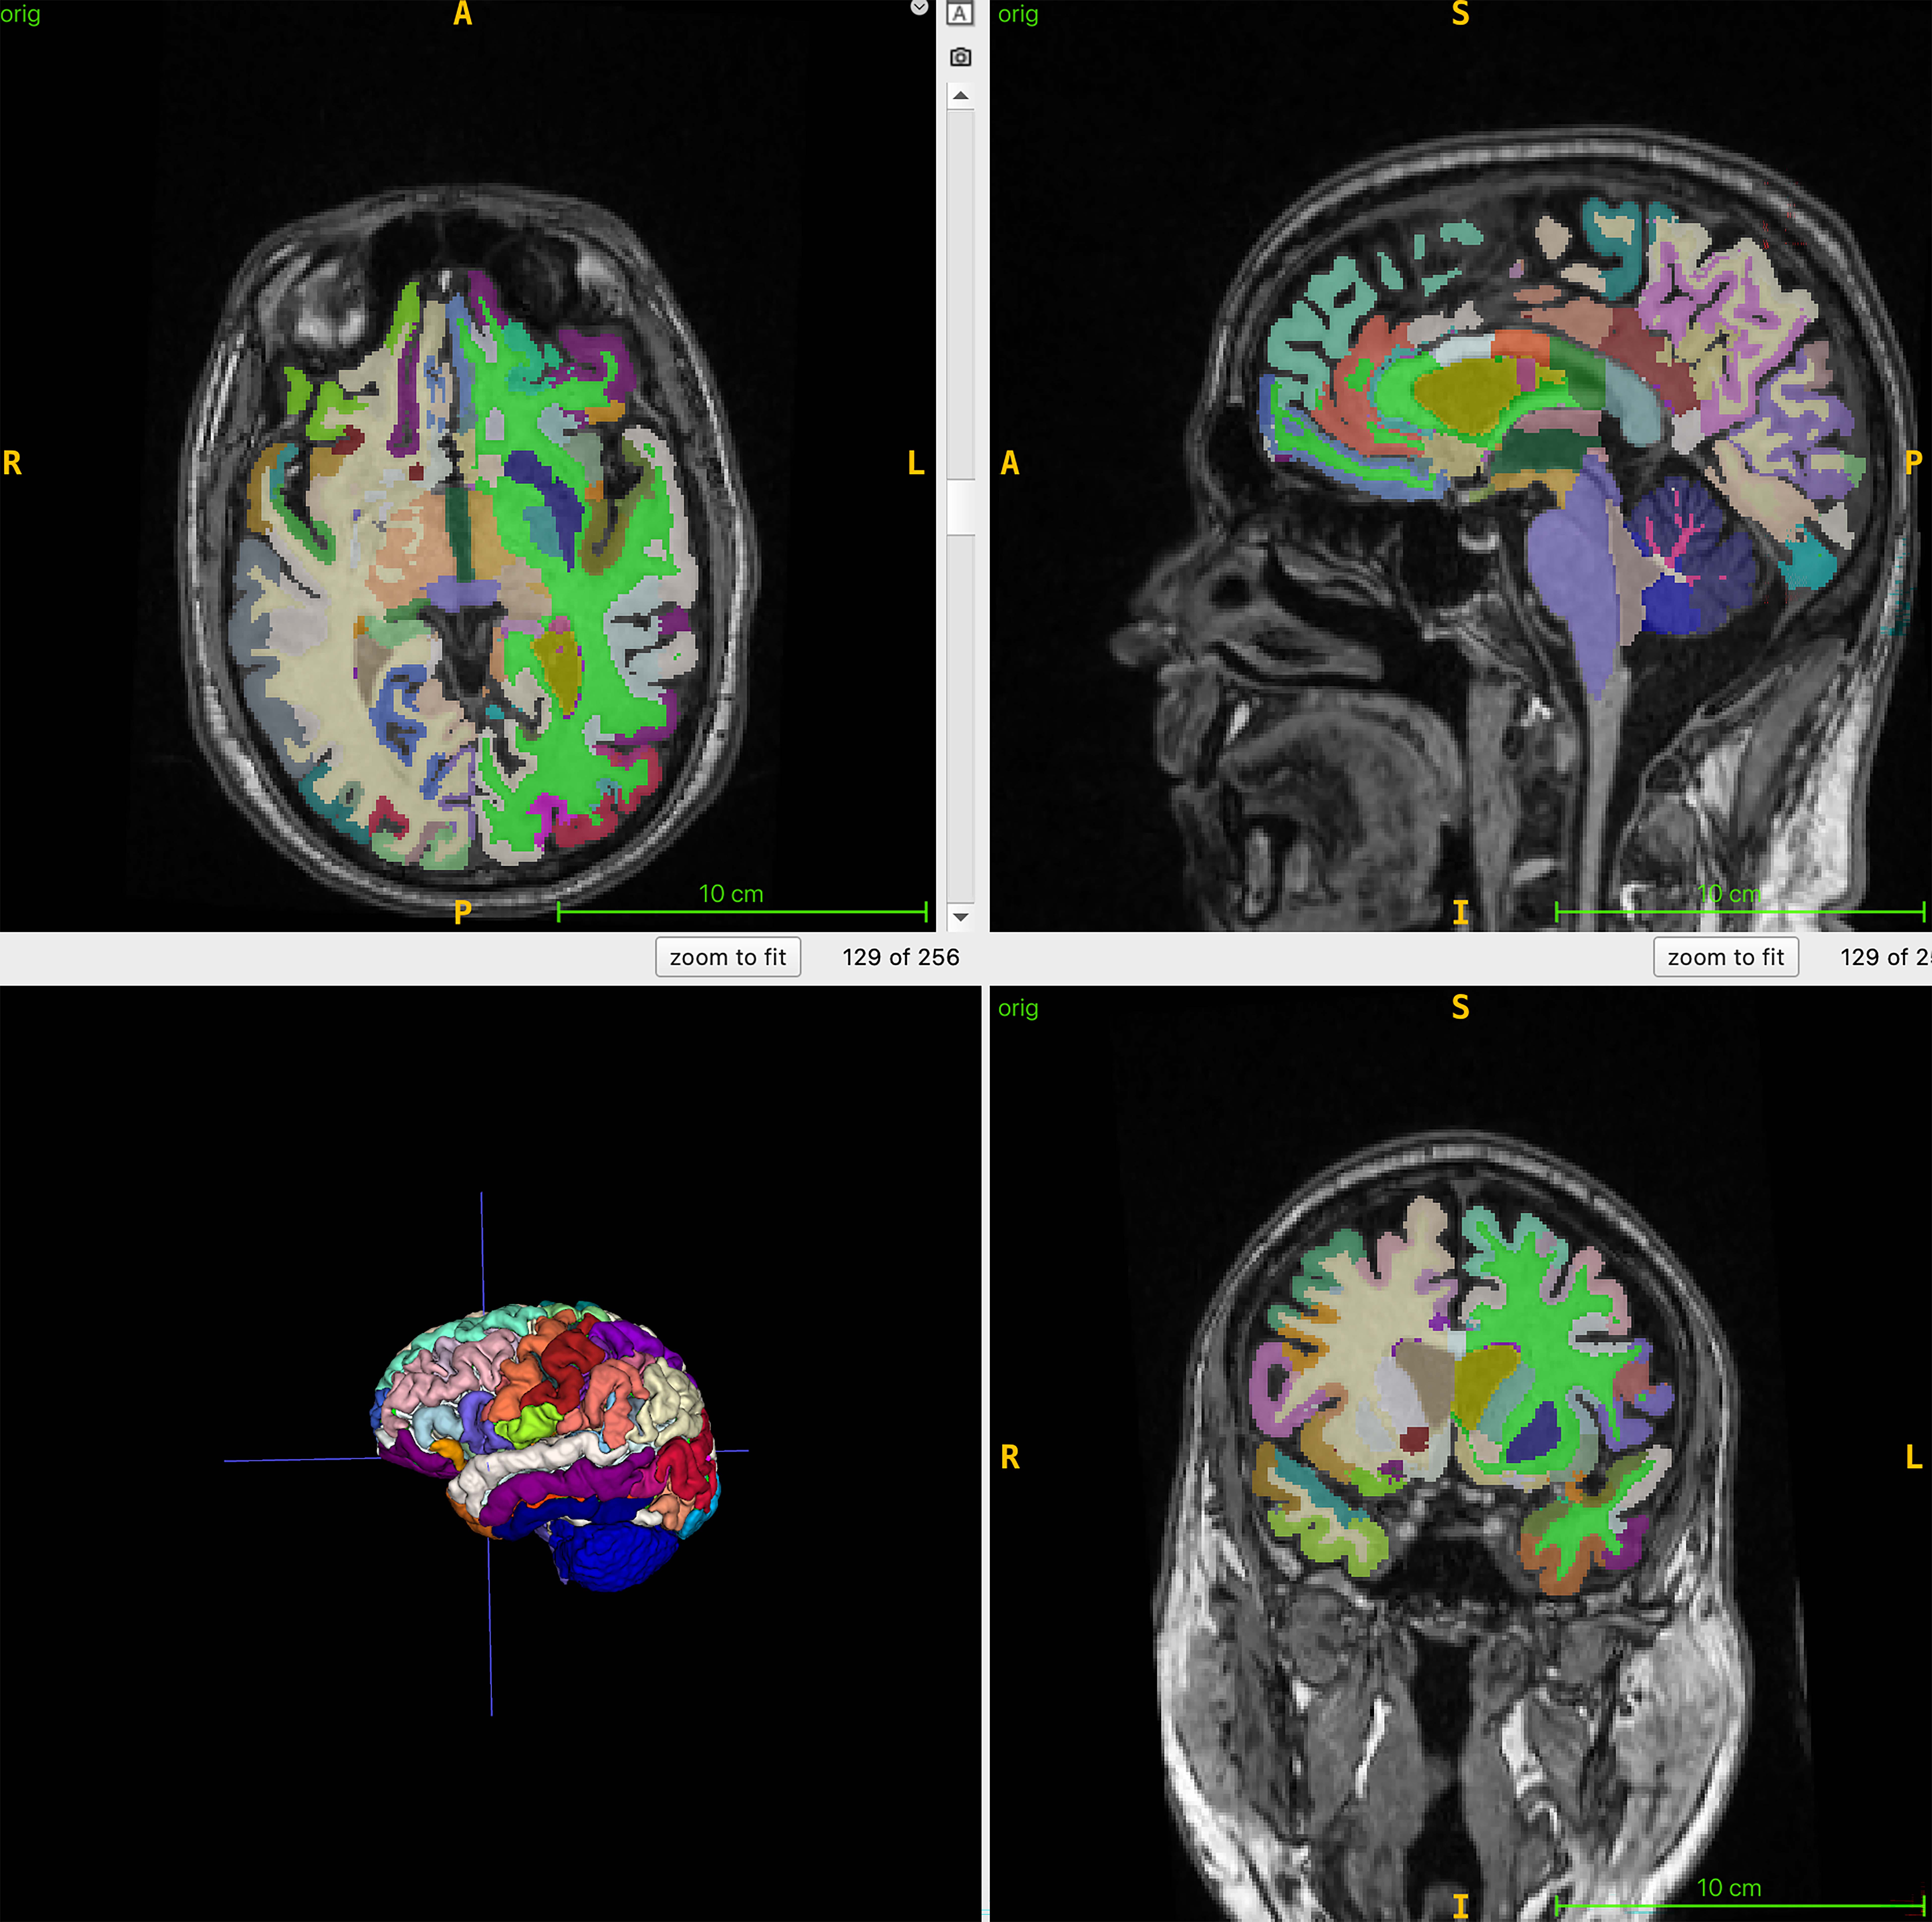

Brain age is the computational estimation of chronological age from a structural MRI scan of the brain. Muscle mass, as tracked by body MRI, can be a surrogate marker for various interventions to reduce frailty and improve brain health, and brain age predicted by structural brain images can lend insight to Alzheimer’s disease risk factors, such as muscle loss.

For the ongoing study, 1,164 healthy individuals (52% women) from four sites were examined with whole-body MRI. The mean chronological age of the participants was 55.17 years. The researchers combined MRI imaging with T1-weighted sequences, a technique that produces images where fat appears bright and fluid appears dark. This allows for optimal imaging of muscle, fat and brain tissue. An artificial intelligence (AI) algorithm was used to quantify total normalized muscle volume, visceral fat (hidden belly fat), subcutaneous fat (fat under the skin) and brain age.